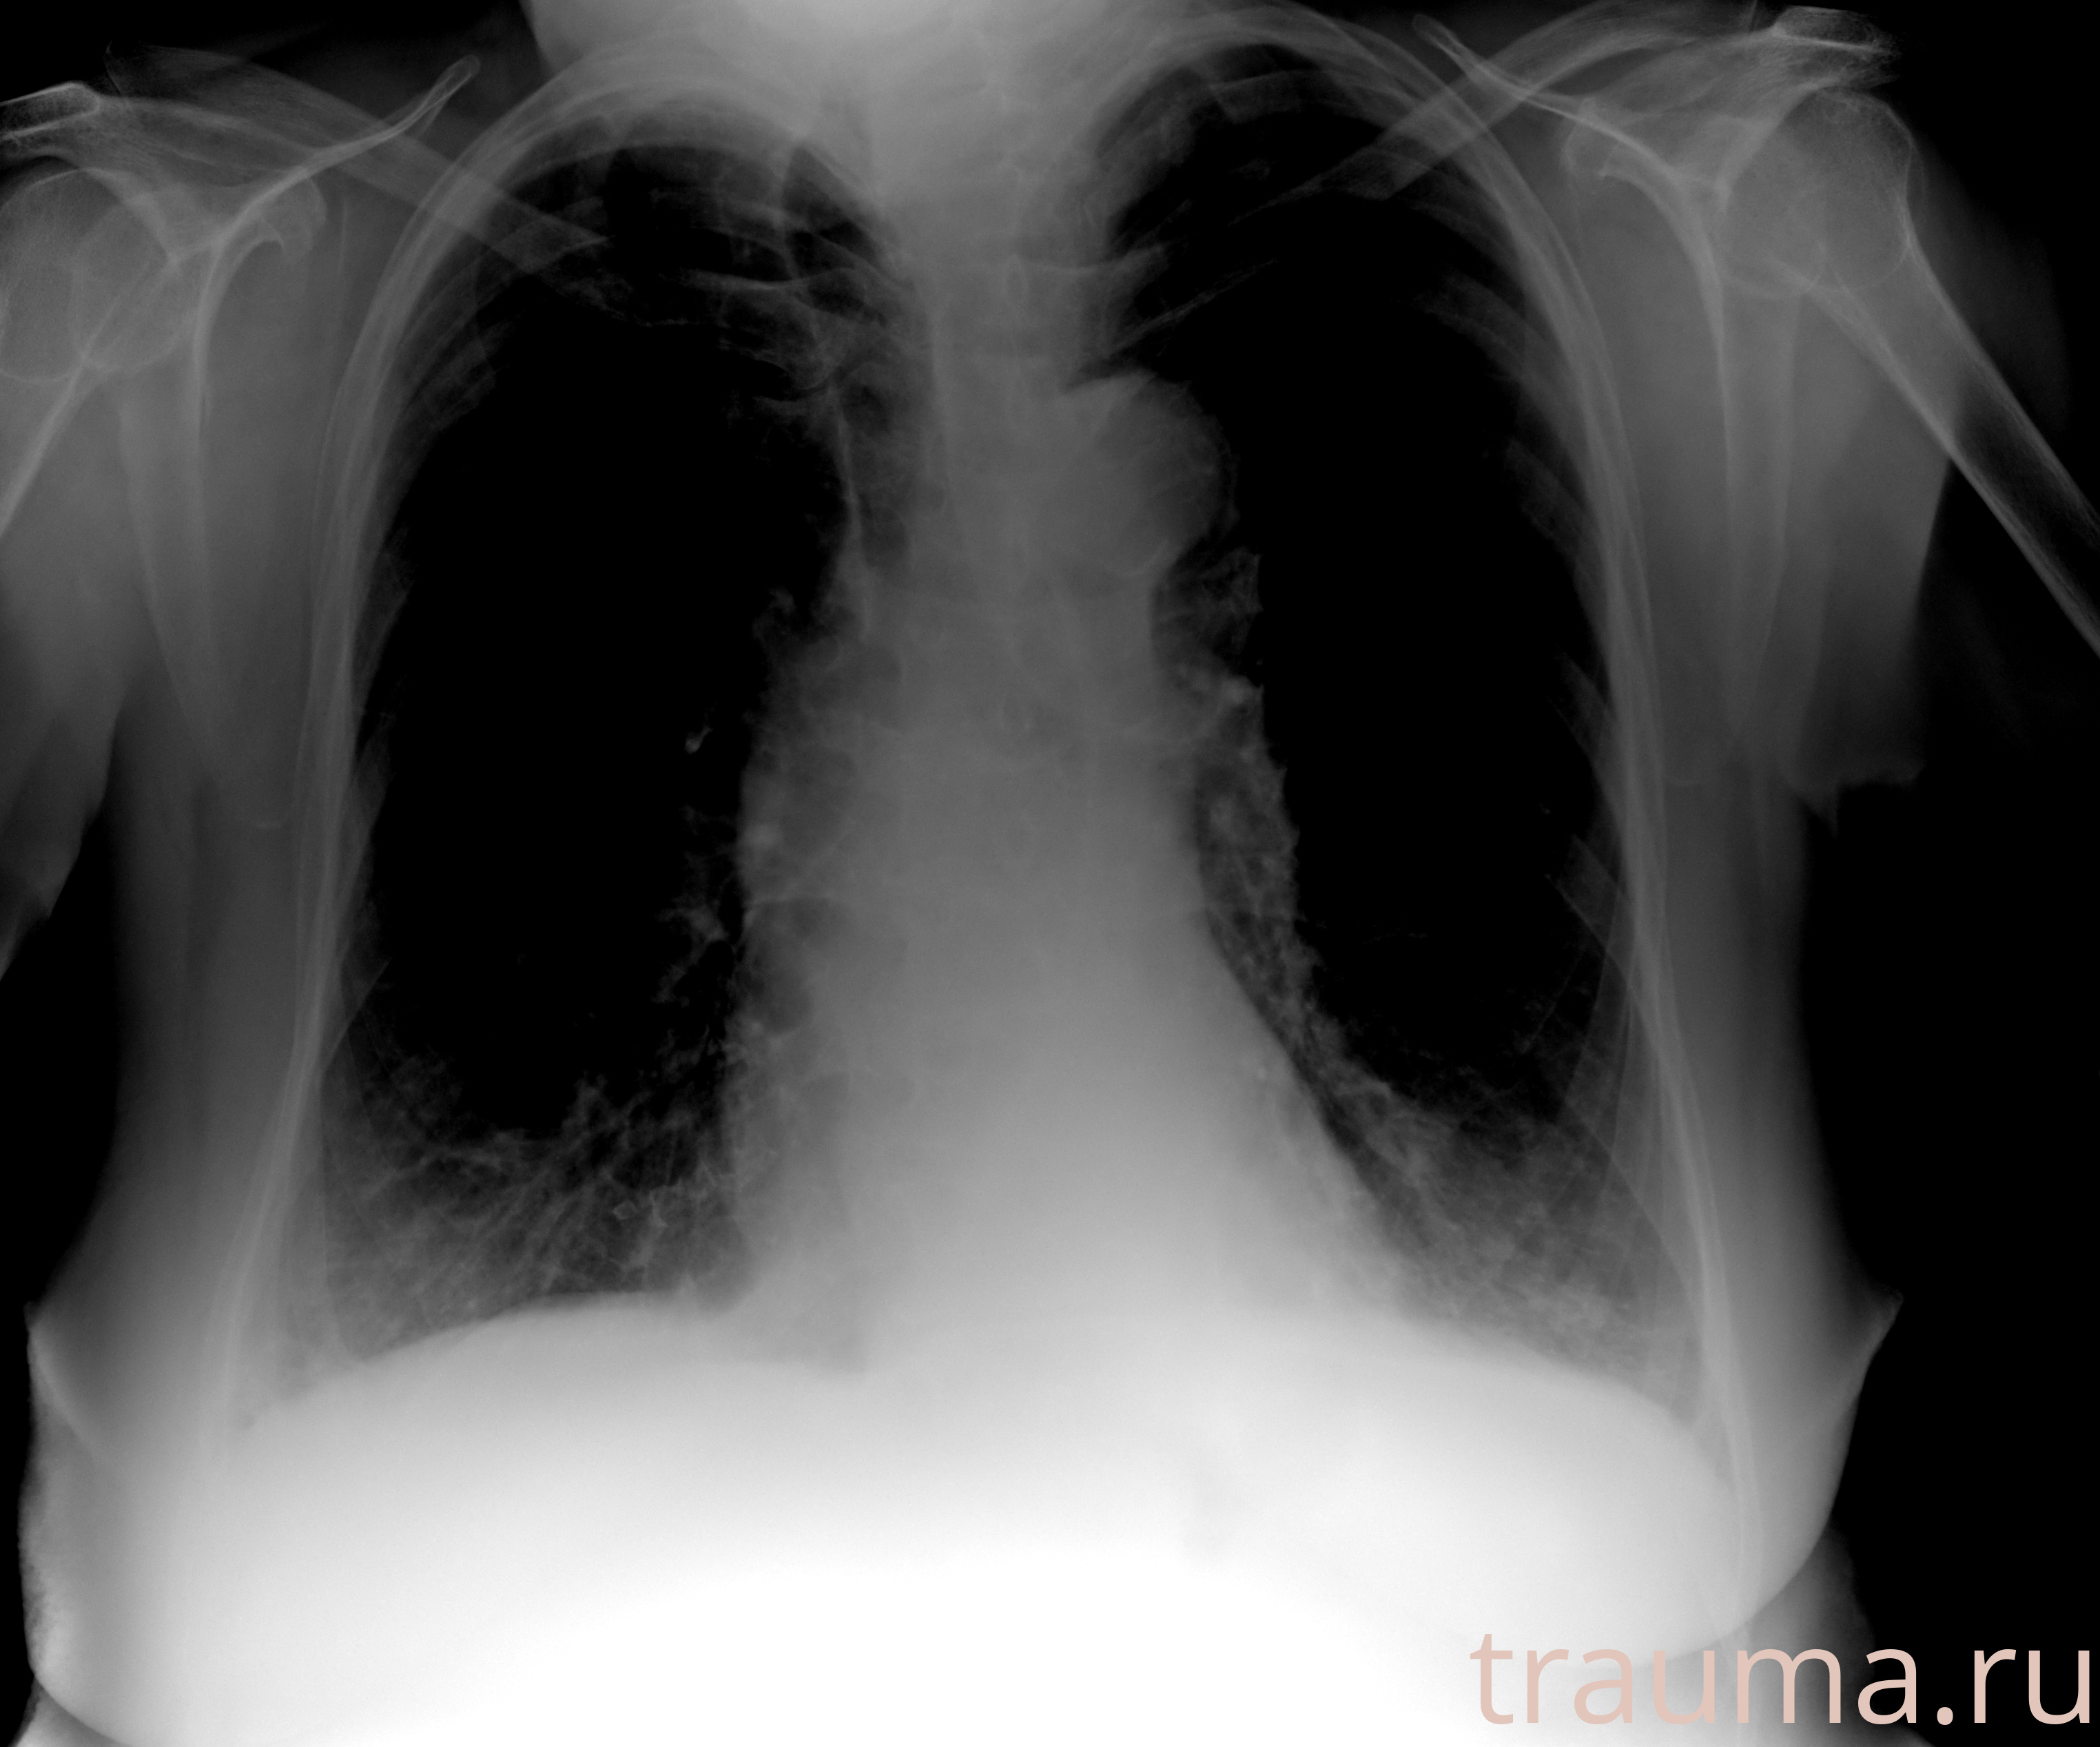

Рентгенограммы

Рентген на дому: по вашему адресу приезжает врач-рентгенолог, травматолог-ортопед с мобильным рентгеновским аппаратом, проводит диагностику травмы или заболевания, делает необходимые рентгенограммы, дает рекомендации по дальнейшему лечению. Получить качественные снимки в домашних условиях возможно благодаря уникальной методике, разработанной МосРентген Центром для института  Склифосовского